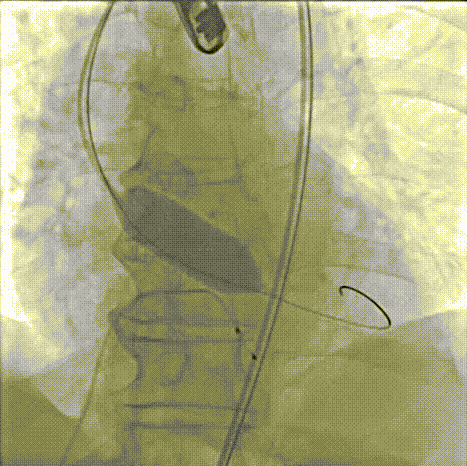

交换猪尾导管测压

瓣膜位置形态良好

术后压差从45 mmHg降至2mmHg